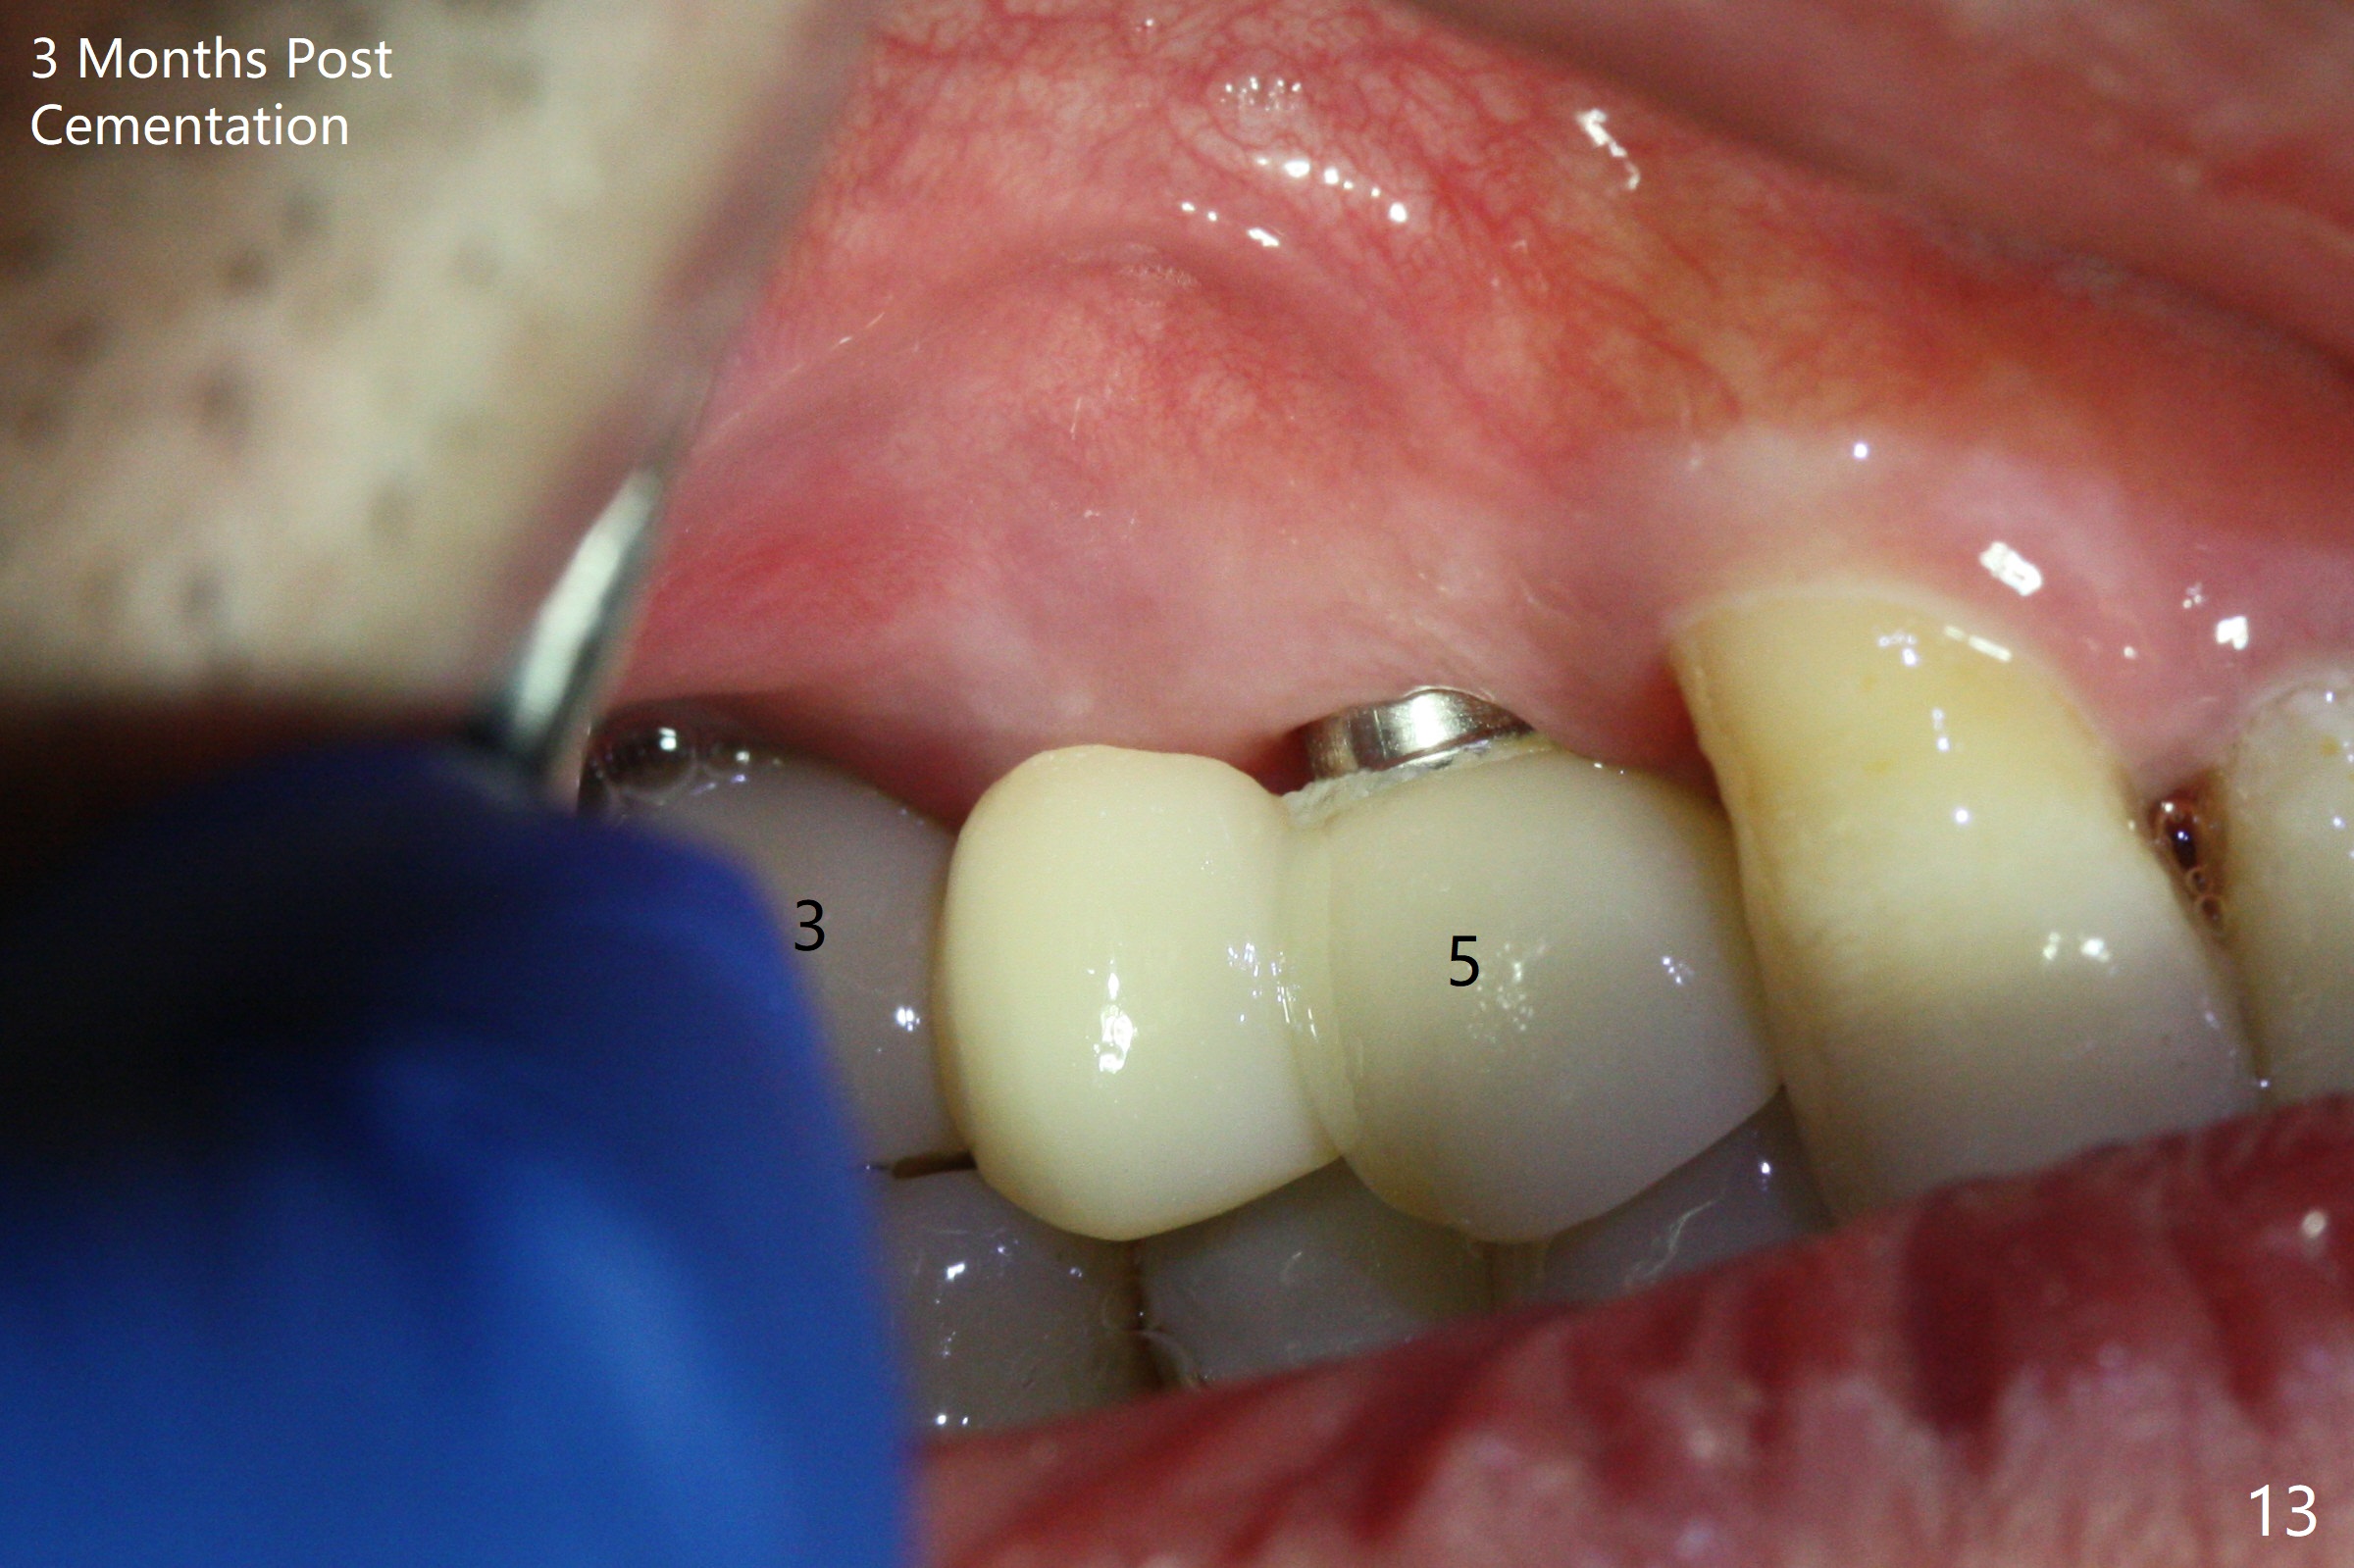

The 36-year-old man (ex-smoker, quit for 4-5 years) insists upon #3 and 5 extraction first for implants, in spite of more severe infection at #7, 14,19,30 (Fig.1-4). The gingiva around #23-26 implants is healthy 3 weeks postop (Fig.5). The initial depths at #3 and 5 are 8.5 mm (bone-level) and 18 mmm (gingiva-level (13 mm (implant length) + 5 mm cuff), respectively. When a drill penetrates the sinus floor, confirm the depth. After use of 3.8 mm drill, 4.5 mm tap drill is inserted at #3 without stability, while a 4.5x13 mm implant is placed at #5 with primary stability (Fig.6,7). Then a 5x11.5 mm is placed at #3 subcrestal proximally after sinus lift with Vanilla graft (without sinus membrane perforation; Fig.8). The implant at #5 is seated ~1 mm deeper (subcrestal mesially (^^); supracrestal distally (^)); allograft is placed around the implants prior to insertion of 6.5x7(5) and 5.5x4(5) mm abutments; last more allograft is added (Fig.9 *, 10). The implants seem to have been osteointegrated 4.5 months postop (Fig.11,12). The gingiva is healthy around the implants without bone loss 3 months post cementation (Fig.13,14).